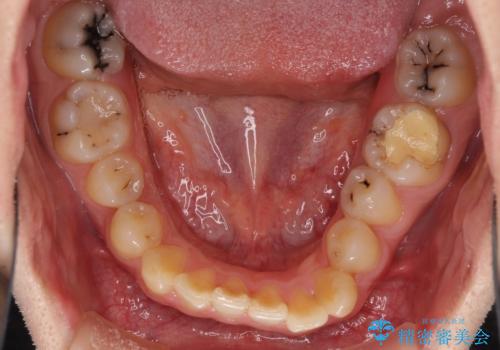

- 前歯のクロスバイトと、大学生のころから放置している虫歯を気にして来院された患者様です。

マウスピースでの矯正治療を希望されていましたが、前歯のクロスバイトは不十分な仕上がりや歯髄壊死などのリスクが高くなるため、術前にワイヤーで大まかに整えてからインビザラインにて矯正治療を行うこととしました。

奥歯の虫歯は抜歯が必要であったので、矯正治療前に抜歯をし、矯正治療と並行してインプラントによる補綴治療を行うこととしました。